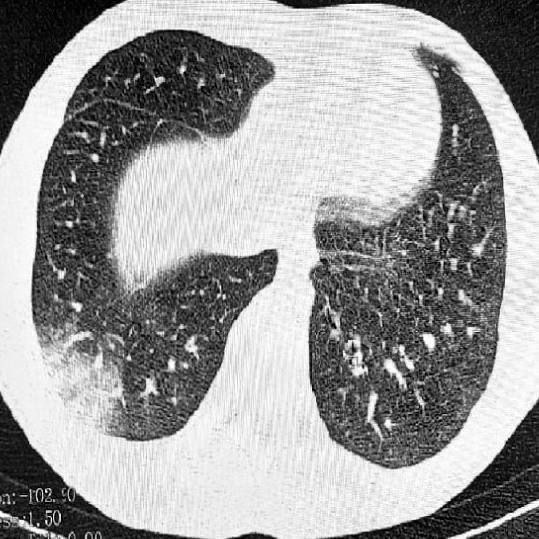

В России впервые выявили «попкорновую болезнь» В Томске двое подростков-вейперов слегли с серьёзными поражениями лёгких: у одного подтвердили EVALI, у второго — токсическое отравление нервной системы. Это заболевание разрушает бронхиолы, а его главный симптом — треск в лёгких, похожий на звук лопающегося попкорна. Лечения нет, а в тяжёлых случаях развивается дыхательная недостаточность, которая может привести к смерти. Попкорновая EVALI болезнь (или E-cigarette or Vaping Product Use-Associated Lung Injury) представляет собой серию легочных заболеваний, связанных с использованием электронных сигарет и вейпов. Этот термин стал известен после вспышки заболеваний в 2019 году, когда врачи начали замечать увеличение случаев пневмонии и других легочных расстройств у пользователей вейпов. Несмотря на название, попкорновая EVALI болезнь не связана с попкорном как продуктом питания, а скорее с веществами, используемыми в некоторых вейпах. ### Причины возникновения Основная причина EVALI з

Это заболевание разрушает бронхиолы, а его главный симптом — треск в лёгких, похожий на звук лопающегося попкорна. Лечения нет, а в тяжёлых случаях развивается дыхательная недостаточность, которая может привести к смерти.

Попкорновая EVALI болезнь (или E-cigarette or Vaping Product Use-Associated Lung Injury) представляет собой серию легочных заболеваний, связанных с использованием электронных сигарет и вейпов. Этот термин стал известен после вспышки заболеваний в 2019 году, когда врачи начали замечать увеличение случаев пневмонии и других легочных расстройств у пользователей вейпов. Несмотря на название, попкорновая EVALI болезнь не связана с попкорном как продуктом питания, а скорее с веществами, используемыми в некоторых вейпах.